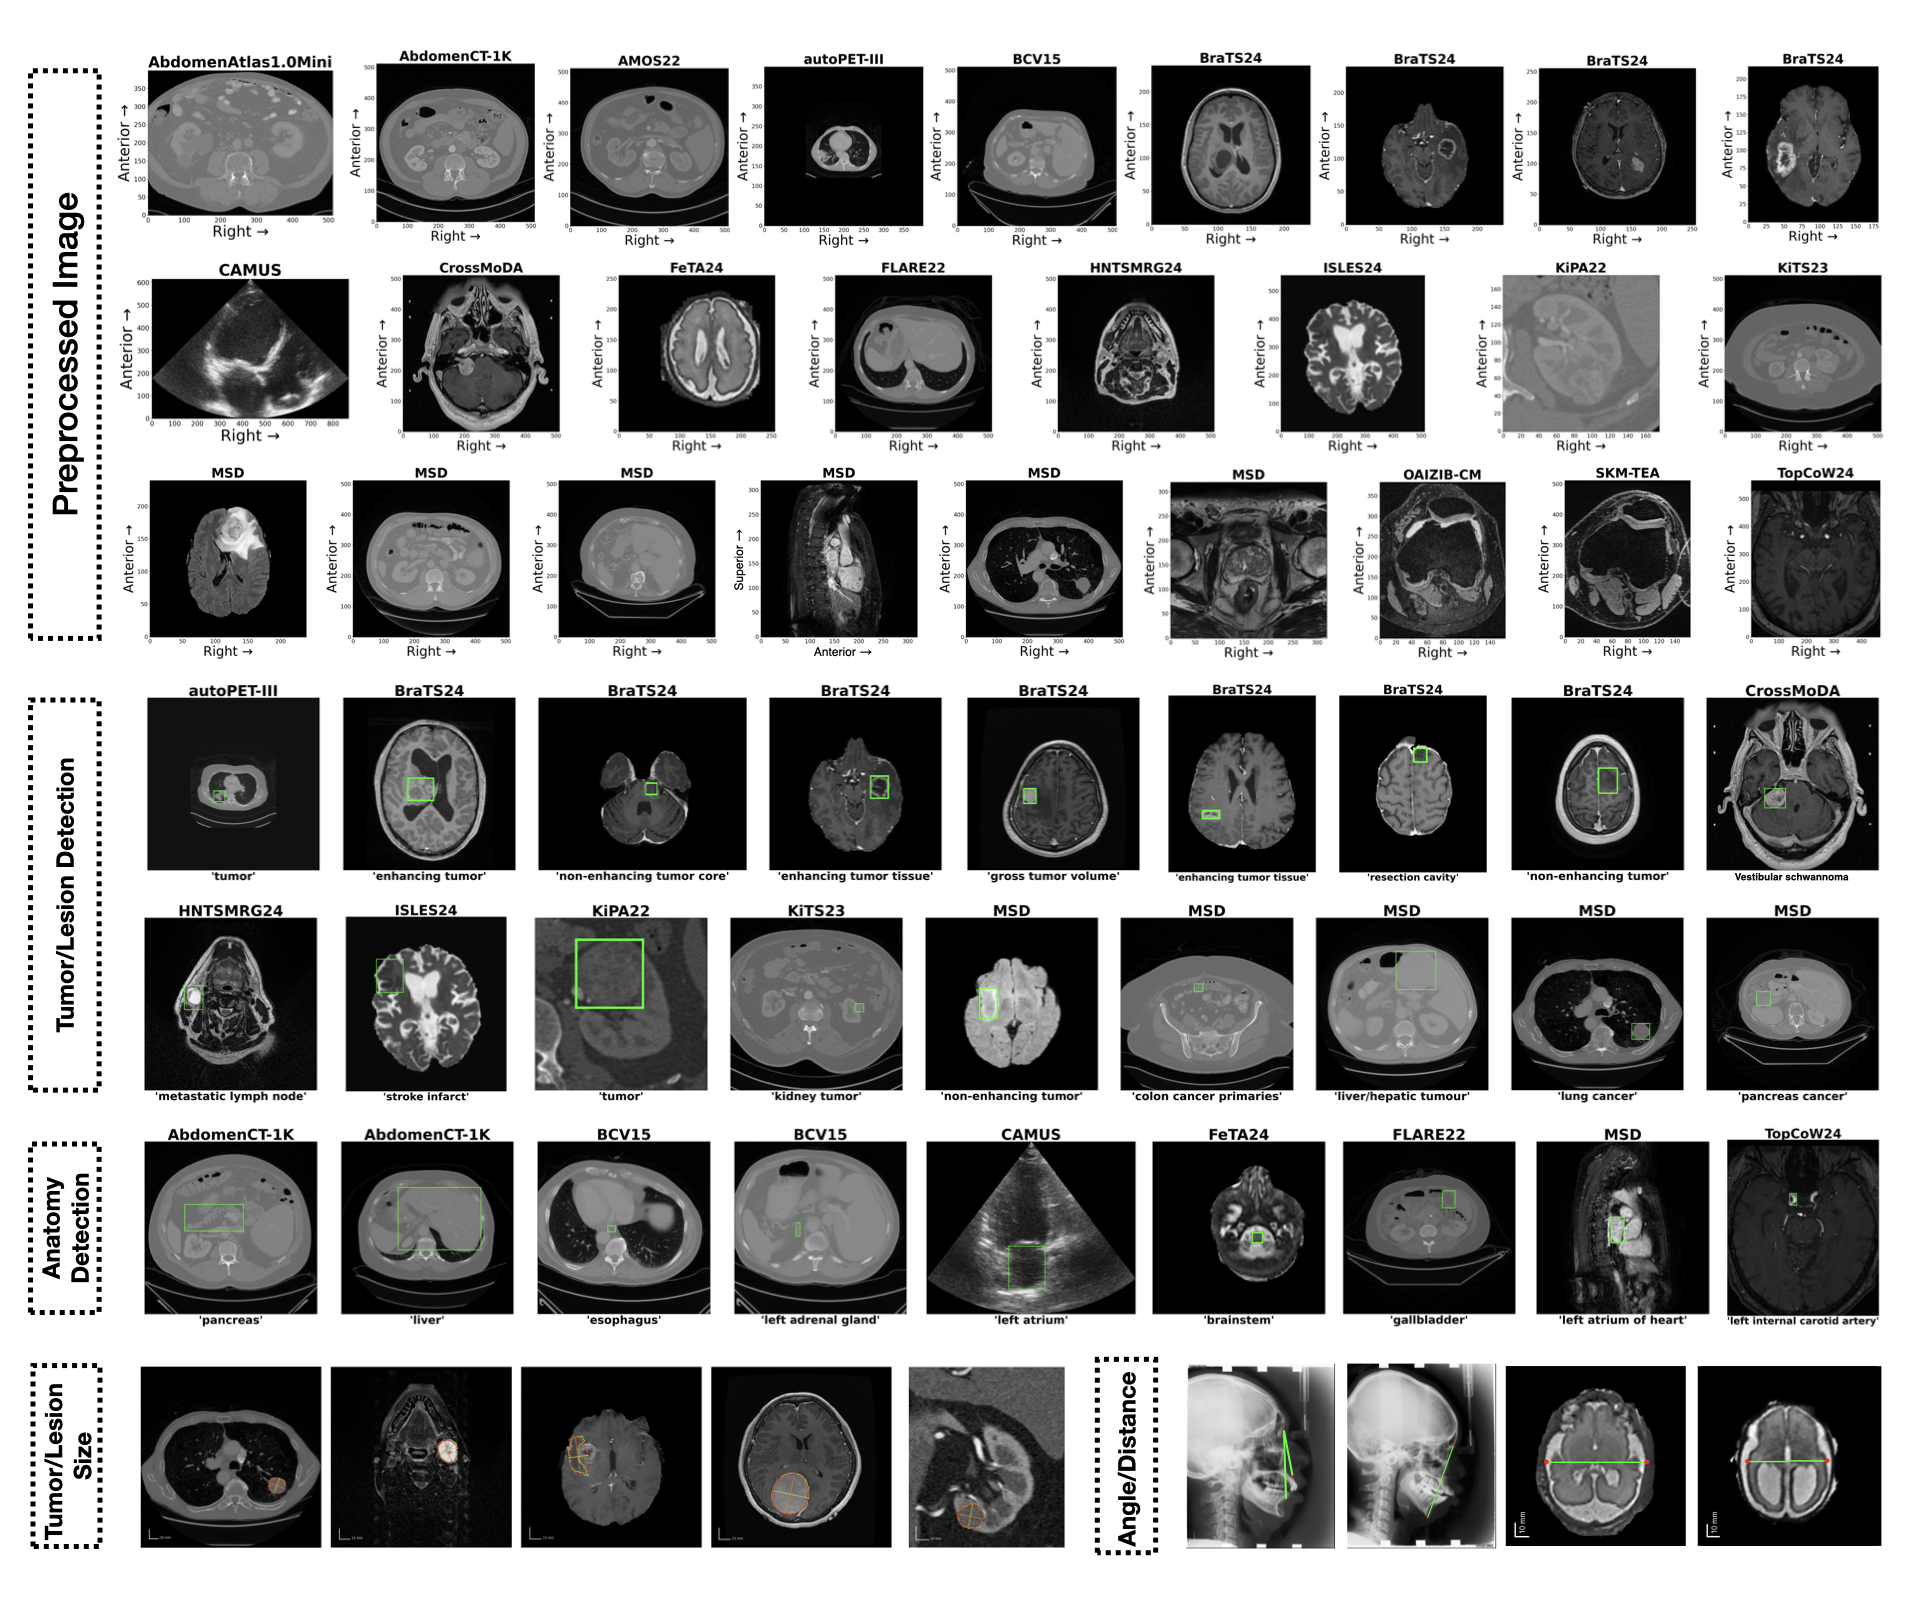

MedVision includes 22 public datasets and 30.8M image-annotation pairs. The dataset is available at here. Details are as follows:

Table 1: The MedVision dataset consists of public medical images and quantitative annotations from this study. MRI: Magnetic Resonance Imaging; CT: Computed Tomography; PET: positron emission tomography; US: Ultrasound; b-box: bounding box; T/L: tumor/lesion size; A/D: angle/distance; HF: HuggingFace; GC: Grand-Challenge; † redistributed.

| Dataset | Anatomy | Modality | Annotation | Availability | Source | # Sample (Train / Test) | ||

|---|---|---|---|---|---|---|---|---|

| b-box | T/L | A/D | ||||||

| AbdomenAtlas | abdomen | CT | b-box | open | HF | 6.8 / 2.9M | 0 | 0 |

| AbdomenCT-1K | abdomen | CT | b-box | open | Zenodo | 0.7 / 0.3M | 0 | 0 |

| ACDC | heart | MRI | b-box | open | HF†, others | 9.5 / 4.8K | 0 | 0 |

| AMOS22 | abdomen | CT, MRI | b-box | open | Zenodo | 0.8 / 0.3M | 0 | 0 |

| autoPEI-III | whole body | CT, PET | b-box, T/L | open | HF†, others | 22 / 9.7K | 0.5 / 0.2K | 0 |

| BCV15 | abdomen | CT | b-box | open | HF†, Synapse | 71 / 30K | 0 | 0 |

| BraTS24 | brain | MRI | b-box, T/L | open | HF†, Synapse | 0.8 / 0.3M | 7.9 / 3.1K | 0 |

| CAMUS | heart | US | b-box | open | HF†, others | 0.7 / 0.3M | 0 | 0 |

| Ceph-Bio-400 | head and neck | X-ray | b-box, A/D | open | HF†, others | 0 | 0 | 5.3 / 2.3K |

| CrossModDA | brain | MRI | b-box | open | HF†, Zenodo | 3.0 / 1.0K | 0 | 0 |

| FeTA24 | fetal brain | MRI | b-box, A/D | registration | Synapse | 34 / 15K | 0 | 0.2 / 0.1K |

| FLARE22 | abdomen | CT | b-box | open | HF†, others | 72 / 33K | 0 | 0 |

| HNTSMRG24 | head and neck | MRI | b-box, T/L | open | Zenodo | 18 / 6.6K | 1.0 / 0.4K | 0 |

| ISLES24 | brain | MRI | b-box | open | HF†, GC | 7.3 / 2.5K | 0 | 0 |

| KiPA22 | kidney | CT | b-box, T/L | open | HF†, GC | 26 / 11K | 2.1 / 1.0K | 0 |

| KiTS23 | kidney | CT | b-box, T/L | open | HF†, GC | 80 / 35K | 5.9 / 2.6K | 0 |

| MSD | multiple | CT, MRI | b-box, T/L | open | others | 0.2 / 0.1M | 5.3 / 2.2K | 0 |

| OAIZIB-CM | knee | MRI | b-box | open | HF | 0.5 / 0.2M | 0 | 0 |

| SKM-TEA | knee | MRI | b-box | registration | others | 0.2 / 0.1M | 0 | 0 |

| ToothFairy2 | tooth | CT | b-box | registration | others | 1.0 / 0.4M | 0 | 0 |

| TopCoW24 | brain | CT, MRI | b-box | open | HF†, Zenodo | 43 / 20K | 0 | 0 |

| TotalSegmentator | multiple | CT, MRI | b-box | open | HF†, Zenodo | 9.6 / 4.0M | 0 | 0 |

| Total | 22 / 9.2M | 23 / 9.6K | 5.6 / 2.4K | |||||